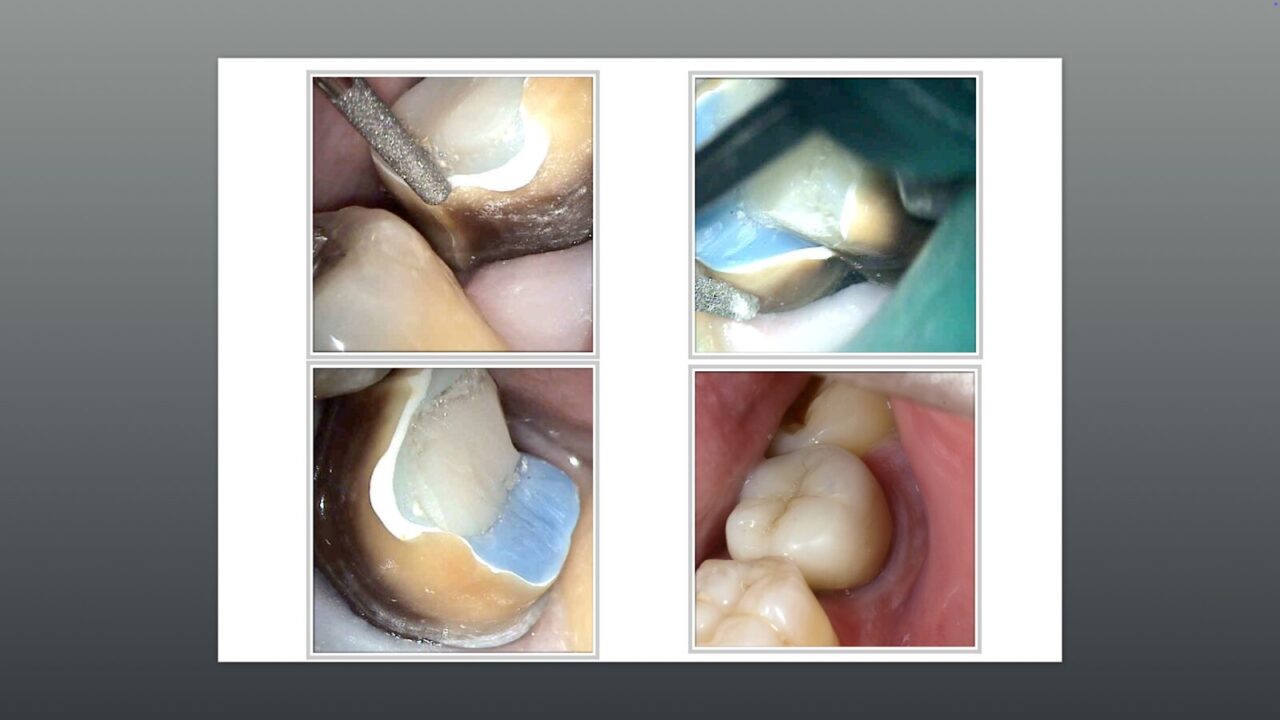

1回法で行ったレントゲン写真。

左から術前のレントゲン、術中根管の内容物を除去した直後のレントゲン写真、バイオセラミックスによる根管充填、レジンコアを行った後のレントゲン写真。

半年間経過を診ていたが、患歯の動揺度は少し減り、頬からの膿も少なくは成っているが、完全に膿が出なくた訳ではありません。

そのため破折線部の感染除去が足りないのではないかと考え、とりあえず近心根のみをもう一度根管治療を行うことにしました。

頬から麻酔液が漏れる様な状態だったので、頬側から根尖部に掻爬を行いました。

バイオセラミックのパテ状のものと従来のもので根管充填を行いました。

根尖から大きくバイオセラミックスが、出ているが生体親和性が高いため問題になりません。

経過を診ていくと根尖部に骨が再生され透過像が消失しています。

仮歯で半年以上経過観察後に最終補綴物をセットしました。